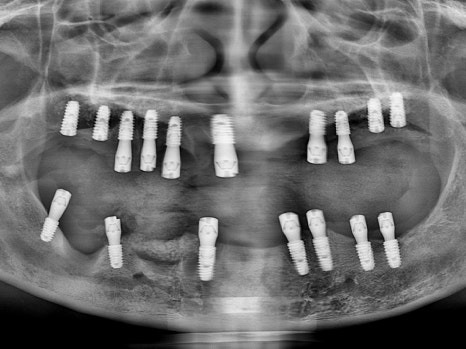

치료 전 파노라마

오래 전 임플란트 치료를 하였지만

염증으로 인해 모두 빠져버린 상황에서

오른쪽 하나만 닿는 어금니로 식사를 하고 계시던 중,

위쪽 치아마저 아파지면서

식사가 아예 불가능하게 되었다고 하셨습니다.

남은 치아는 모두 발치해야 하는 상황,

수면마취로 17개의 임플란트를 식립하였고,

CT 분석을 통해 틀니가 아닌

8개의 전체임플란트를